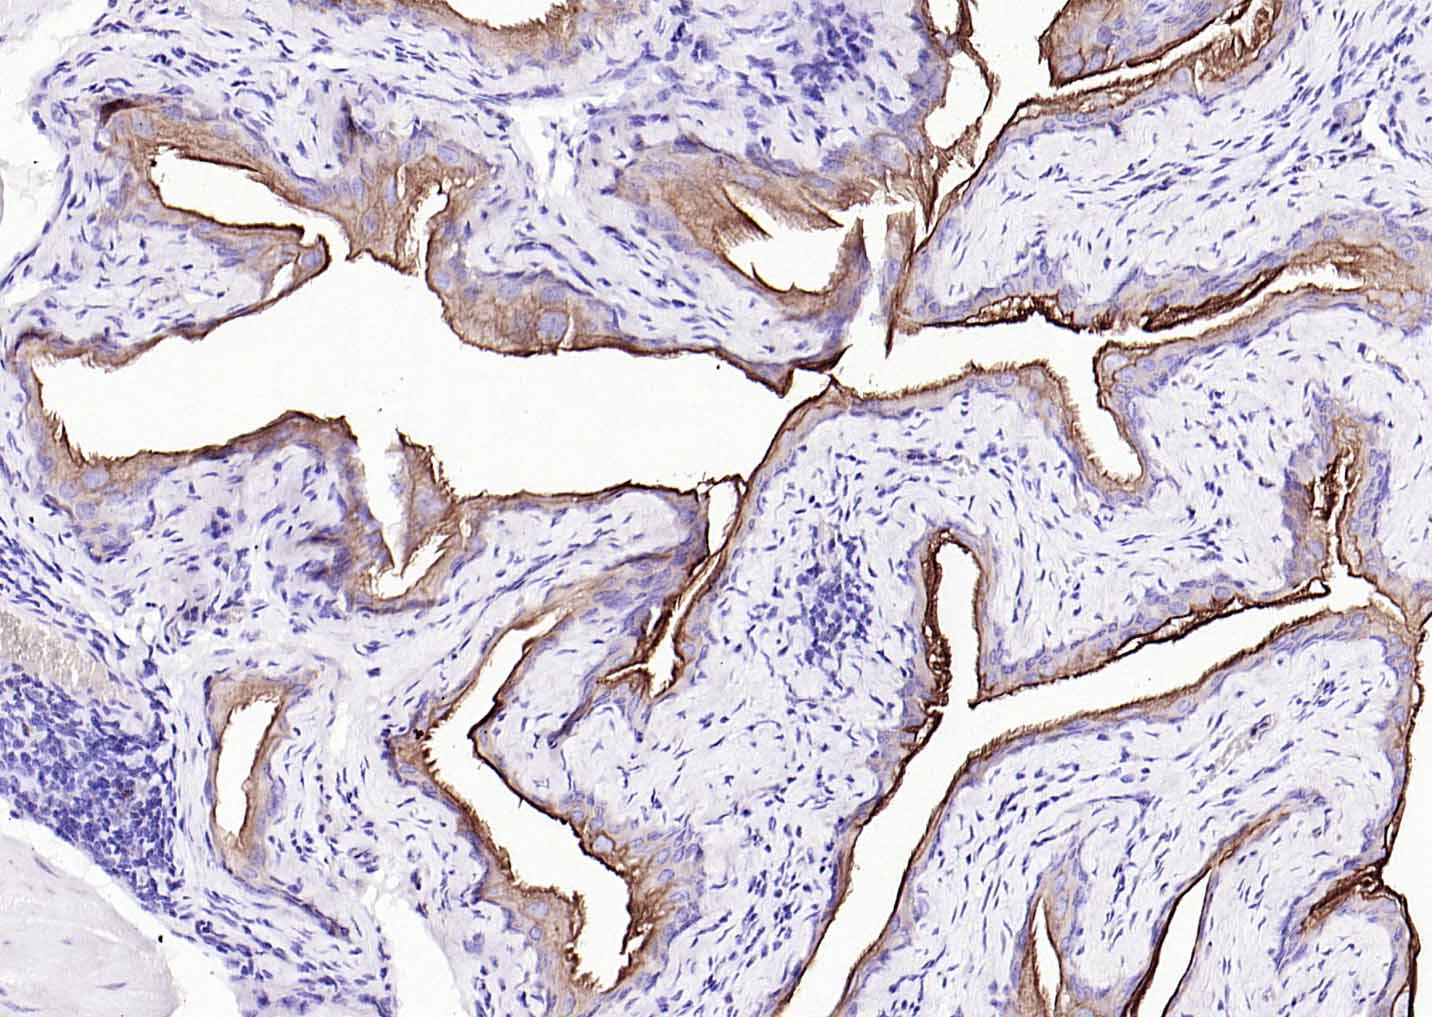

Paraformaldehyde-fixed, paraffin embedded (human breast); Antigen retrieval by boiling in sodium citrate buffer (pH6.0) for 15min; Block endogenous peroxidase by 3% hydrogen peroxide for 20 minutes; Blocking buffer (normal goat serum) at 37°C for 30min; Antibody incubation with (CK7) Monoclonal Antibody, Unconjugated (bsm-33060M) at 1:200 overnight at 4°C, followed by operating according to SP Kit(Mouse)(sp-0024) instructionsand DAB staining.